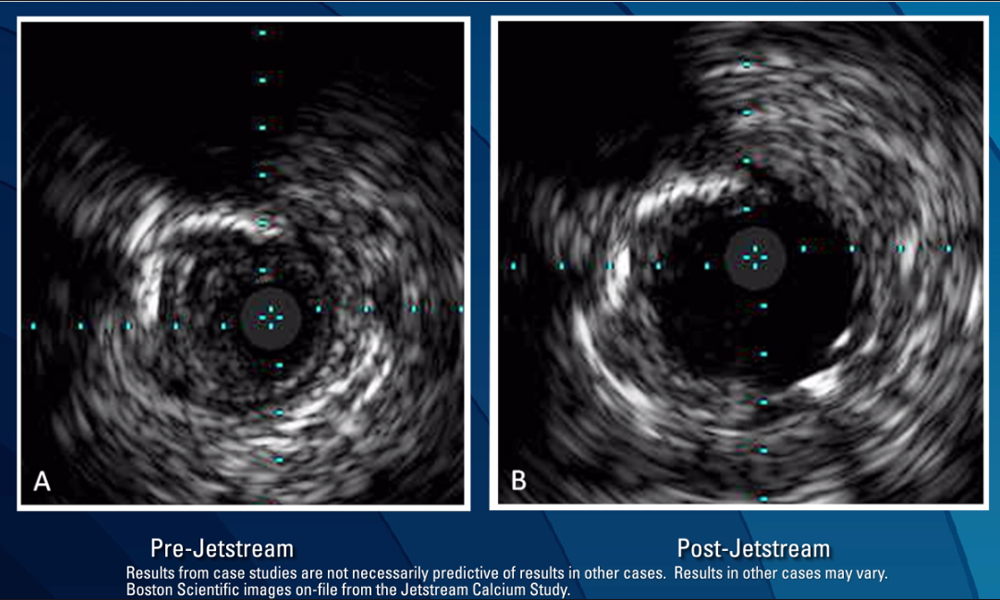

Feb 07, 2016Key Learnings From Jetstream Atherectomy Calcium Study

Insights on removing severe superficial calcium to achieve significant luminal gain in femoropopliteal arteries PDF, 6.0 MB